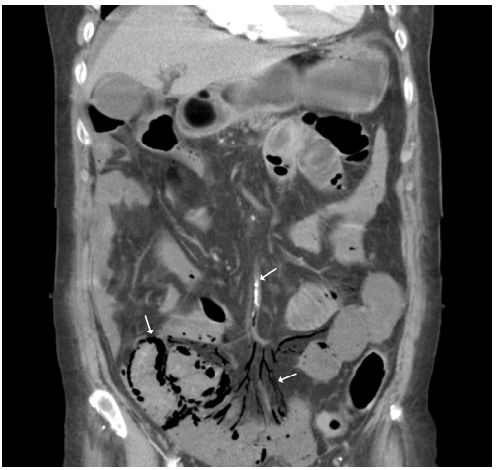

病人的腹部電腦斷層如下:

問題3: 腹部斷層影像中顯示的現象為何?臨床診斷為何?(20 %)